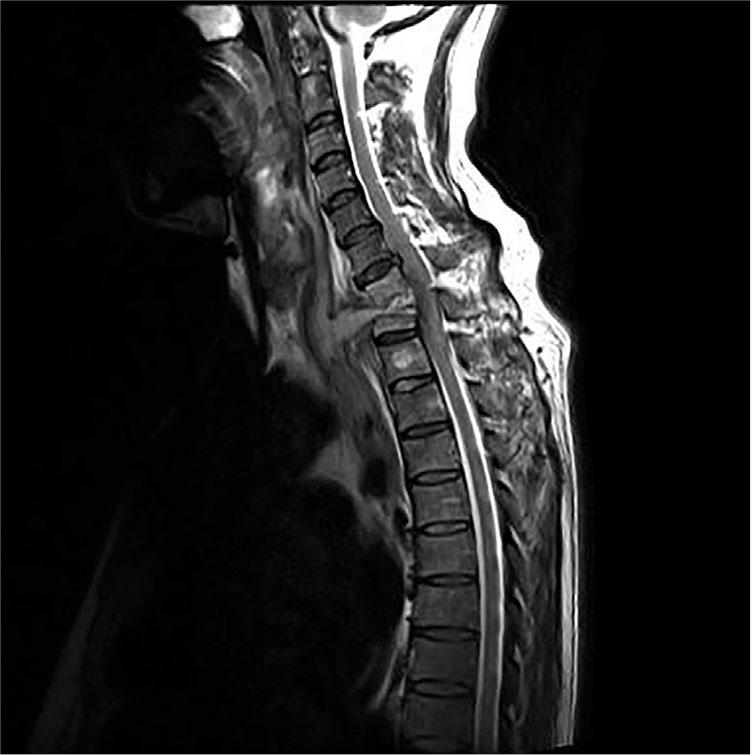

Figure 3

MR result of the thoracic vertebra before the operation.